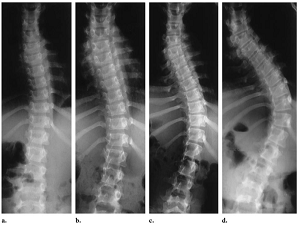

Skolyoz hastalığında erken tanı ve ameliyat çok önemli